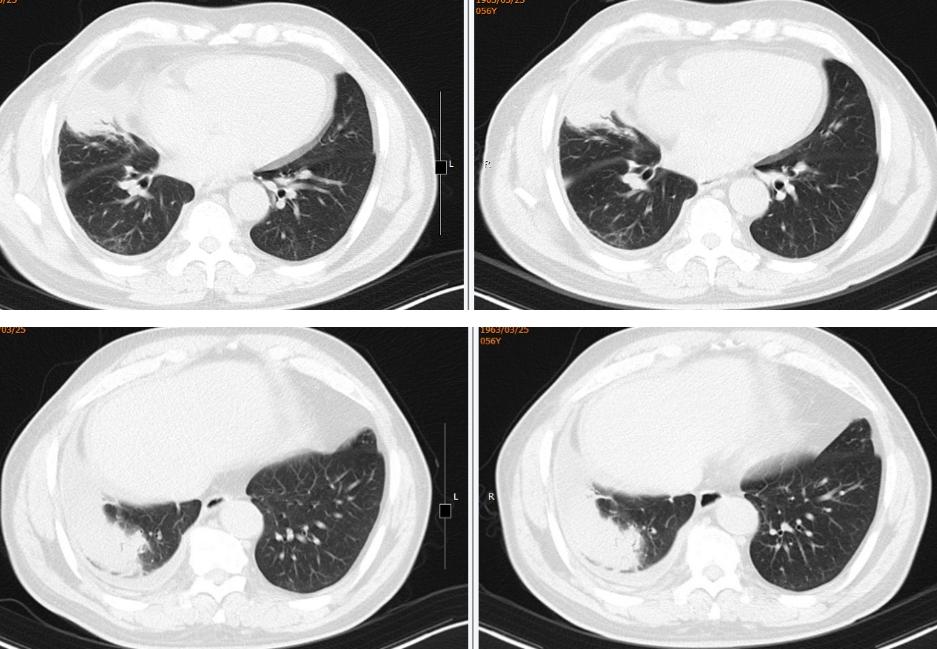

(从左至右)初诊、1月后、4月后:

图14:2019-09-16胸部CT(1月后):右肺中下叶团块、索条灶,右侧胸腔积液,较2019-08-14老片病灶略吸收,积液减少。2019-12-16胸部CT(4月后):右肺中下叶团块、索条灶,右侧胸腔积液,较2019-09-16老片病灶略吸收,积液减少。